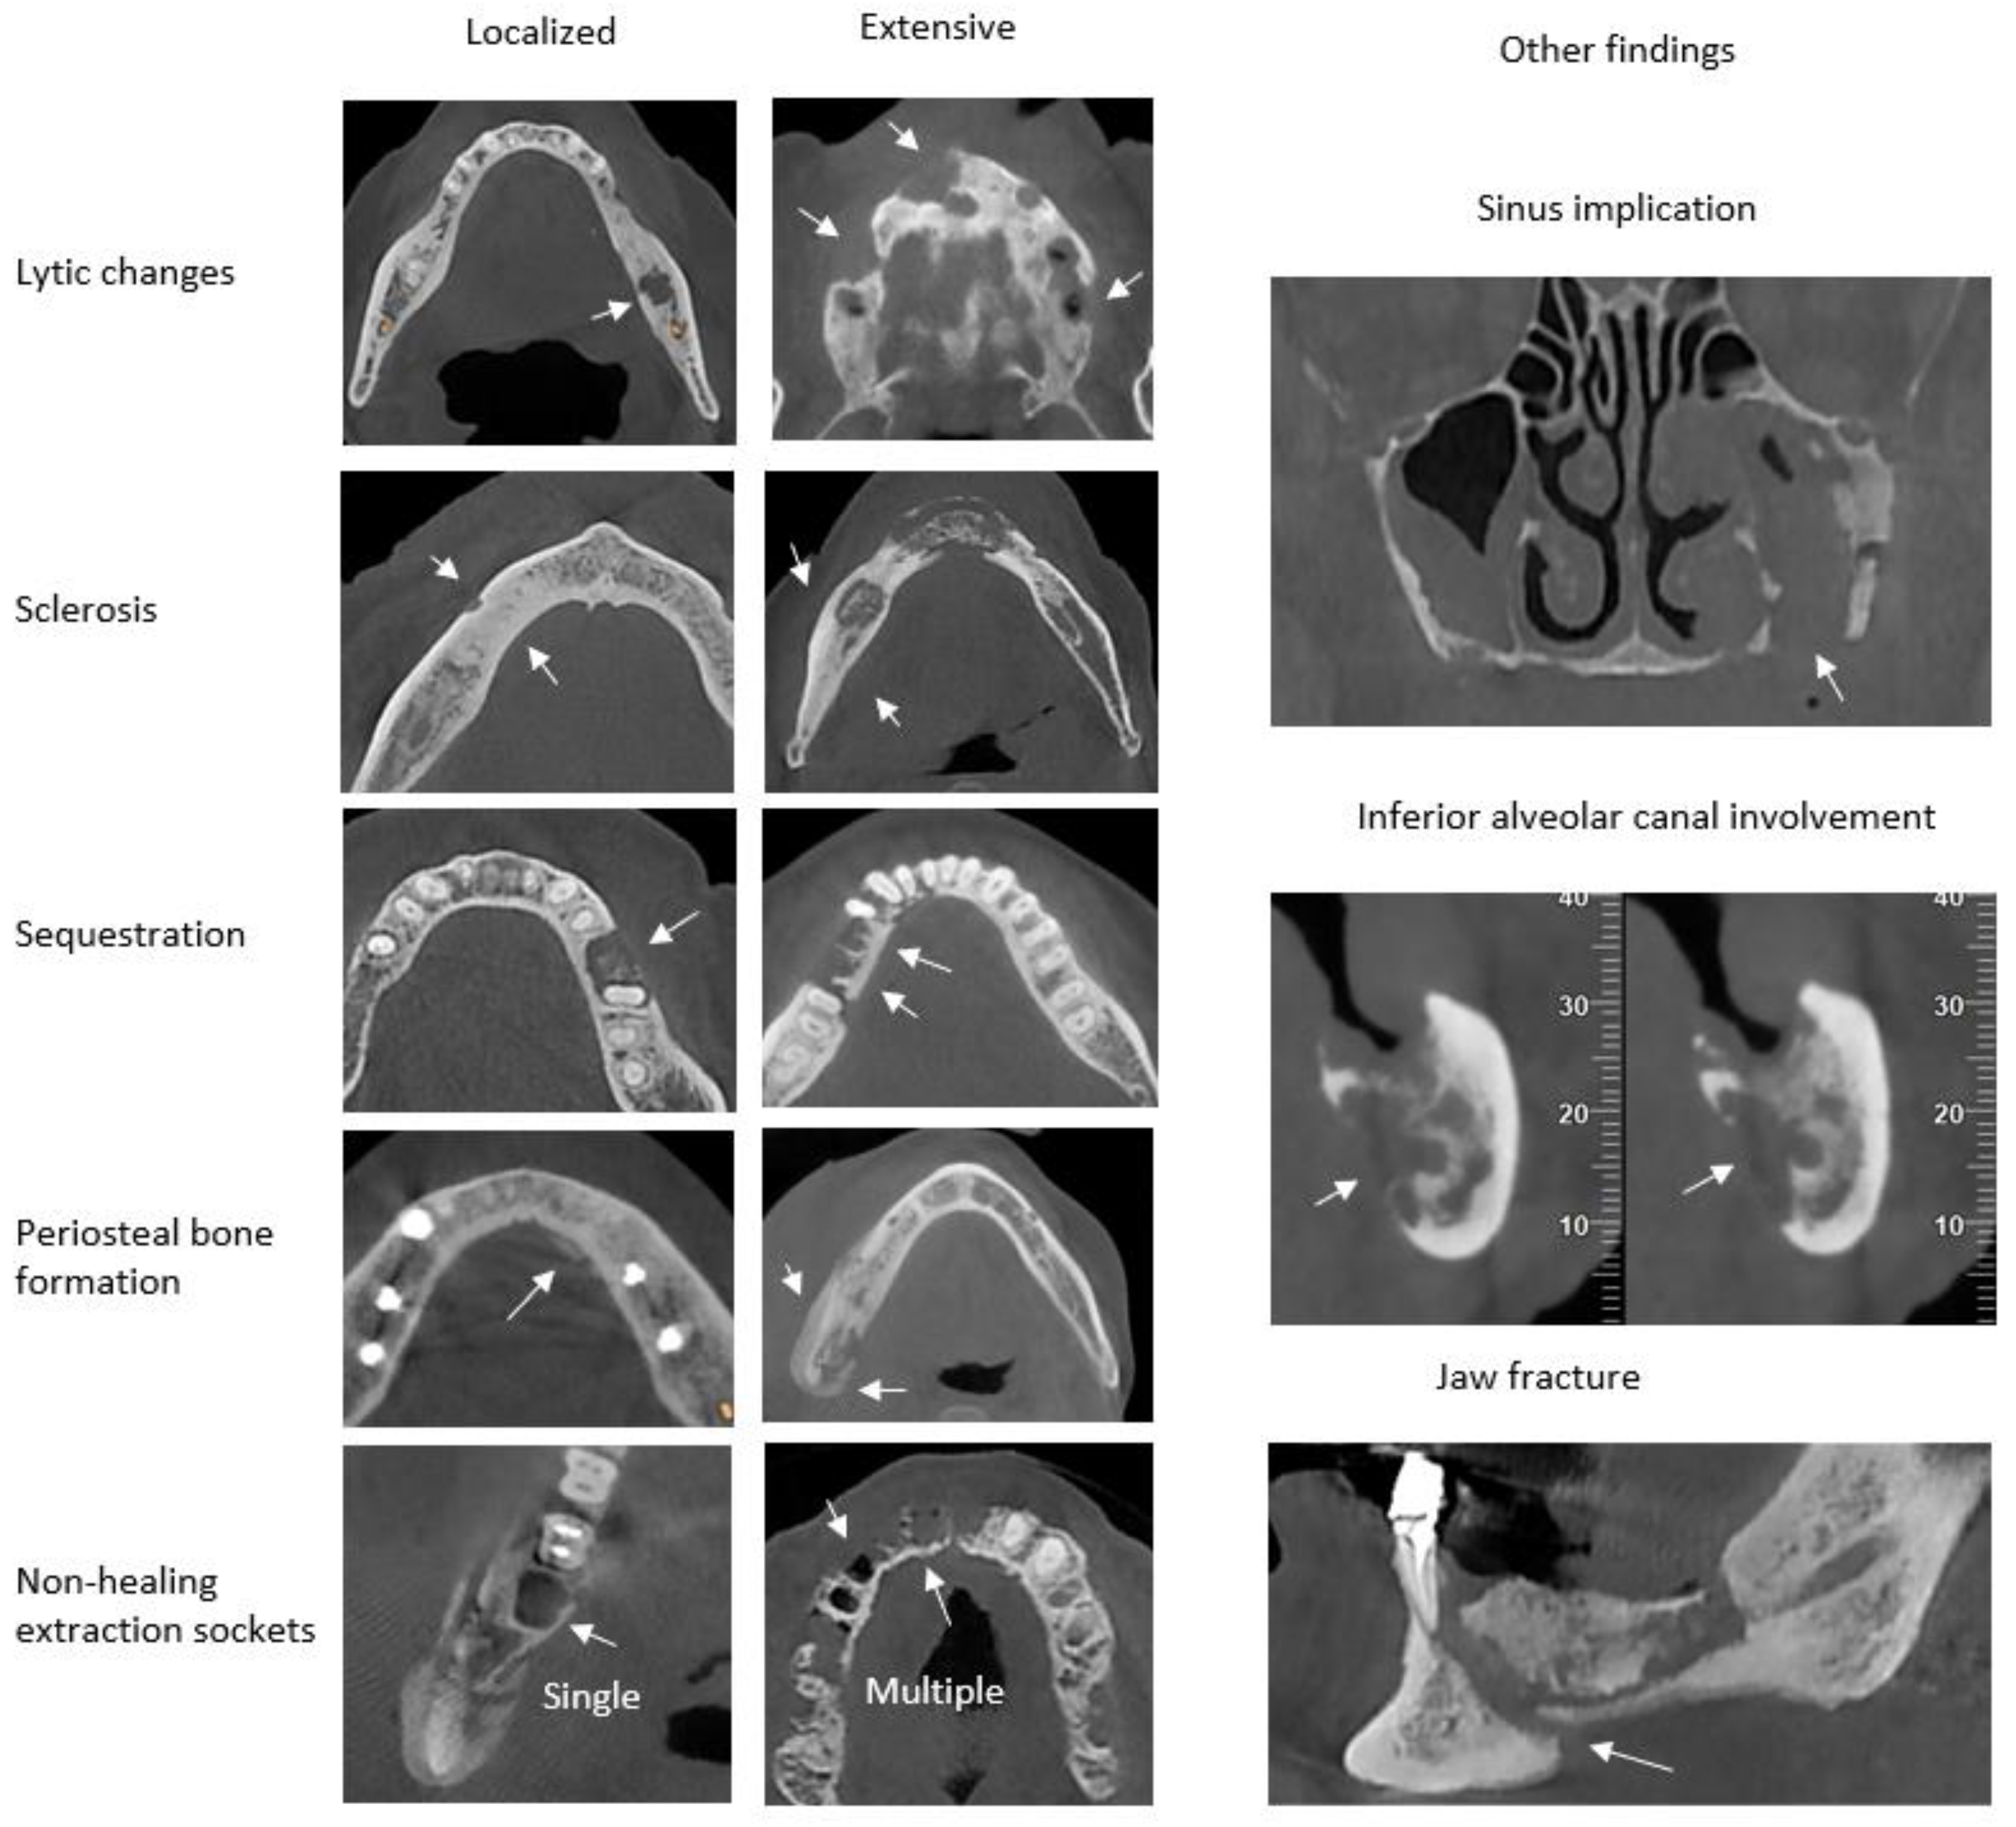

| Lytic changes (n,%) | 0 | 6 (31,6) | 2 (12,5) | 1 (5,9) | 0,003* |

| 1 | 8 (42,1) | 3 (18,8) | 1 (5,9) | ||

| 2 | 5 (26,3) | 11 (68,8) | 15 (88,2) | ||

| Sclerosis (n,%) | 0 | 5 (26,3) | 4 (25,0) | 4 (23,5) | 0,737 |

| 1 | 2 (10,5) | 2 (12,5) | 0 (0,0) | ||

| 2 | 12 (63,2) | 10 (62,5) | 13 (76,5) | ||

| Periosteal bone formation (n,%) | 0 | 13 (68,4) | 10 (62,5) | 8 (47,1) | 0,499 |

| 1 | 1 (5,3) | 3 (18,8) | 2 (11,8) | ||

| 2 | 5 (26,3) | 3 (18,8) | 7 (41,2) | ||

| Sequestration (n, %) | 0 | 15 (78,9) | 7 (43,8) | 2 (11,8) | <0,001* |

| 1 | 0 (0,0) | 3 (18,8) | 1 (5,9) | ||

| 2 | 4 (21,1) | 6 (37,5) | 14 (82,4) | ||

| Non-healing extraction sockets (n, %) | 0 | 11 (57,9) | 8 (50,0) | 8 (47,1) | 0,934 |

| 1 | 5 (26,3) | 4 (25,0) | 6 (35,3) | ||

| 2 | 3 (15,8) | 4 (25,0) | 3 (17,6) | ||

| Other findings | |||||

| Sinus implication (n,%) | 0 | 3 (60,0) | 2 (66,7) | 0 (0,0) | 0,145 |

| 1 | 2 (40,0) | 1 (33,3) | 5 (100,0) | ||

| Inferior alveolar canal involvement (n, %) | 0 | 14 (100,0) | 13 (100,0) | 2 (16,7) | <0,001* |

| 1 | 0 (0,0) | 0 (0,0) | 10 (83,3) | ||

| Jaw fracture (n, %) | 0 | 19 (100,0) | 16 (100,0) | 15 (88,2) | 0,193 |

| 1 | 0 (0,0) | 0 (0,0) | 2 (11,8) | ||